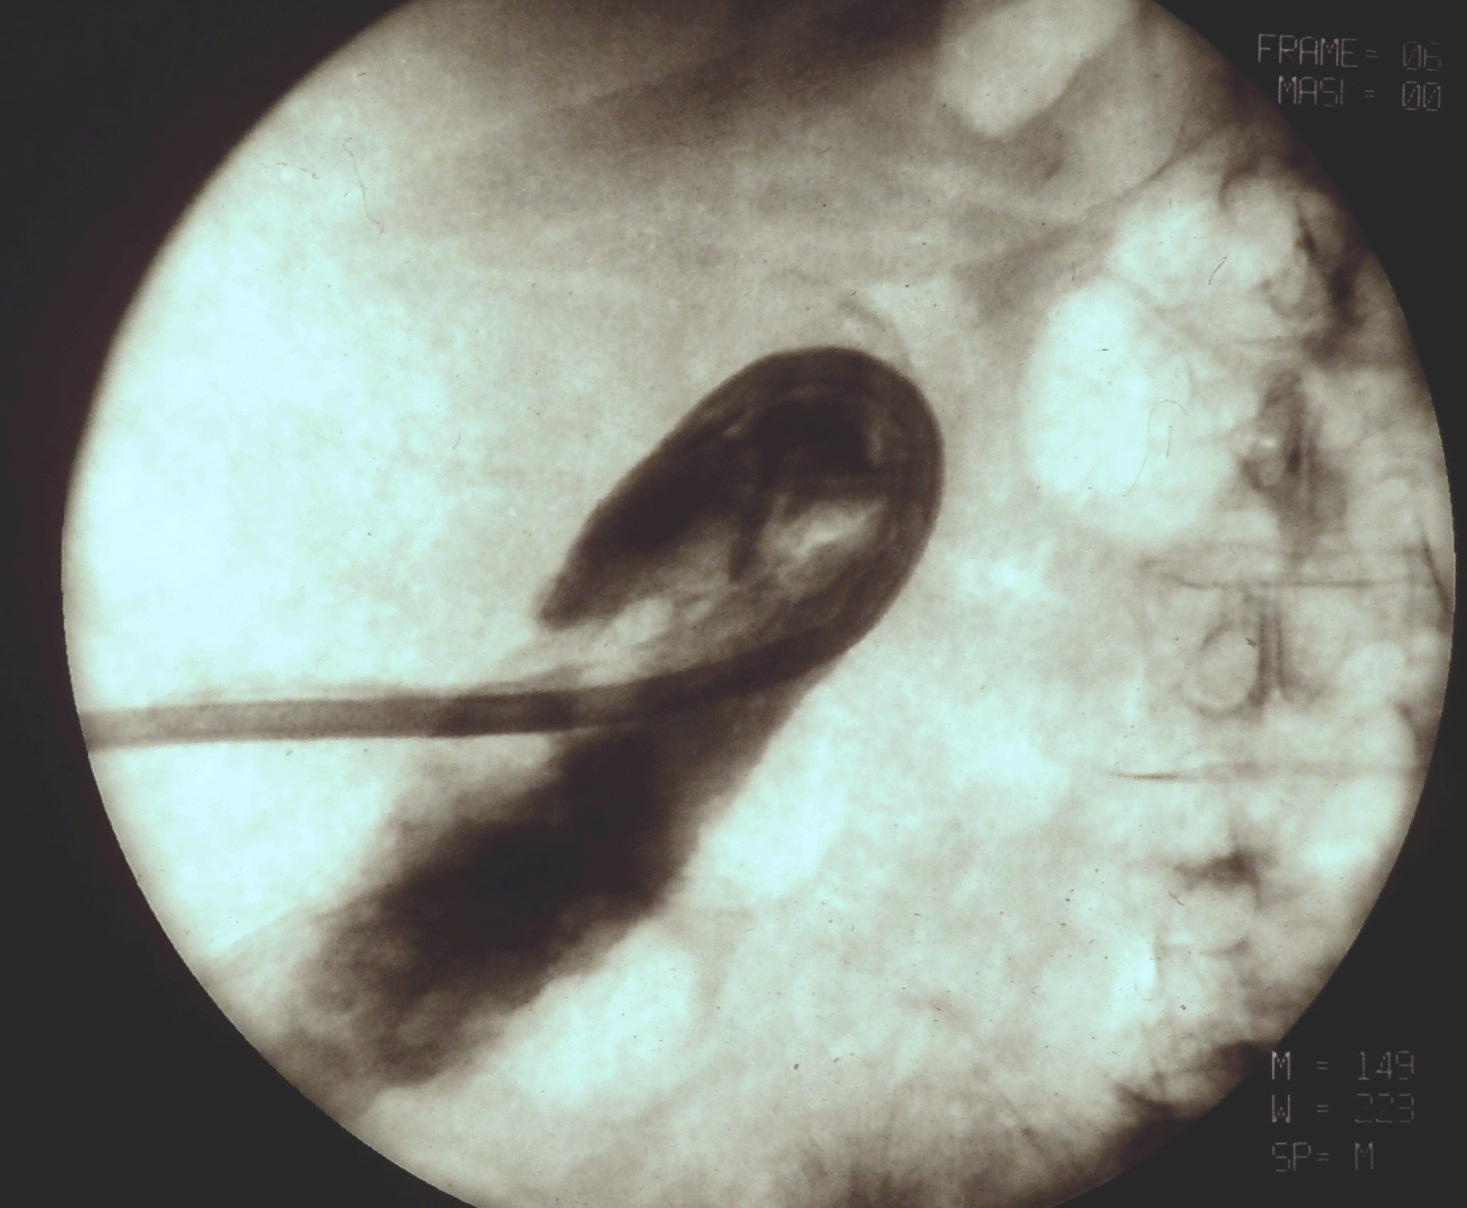

TAE (Transcatheter Arterial Embolization) and TACE (Transcatheter Arterial ChemoEmbolization) are methods with which the supplying artery/arteries of the tumor are selectively approached through the branches of the hepatic artery. When the catheter is in position the tumor branches are injected with a special, oily contrast material, Lipiodol (TAE). The injected material is used as an embolization material (figure 18.), other chemotherapeutical drugs (5-Fluoro-Uracil, Epirubicin, Cisplatin, Mytomicin-C) can also be used (TACE) (figure 19.).

Image

Figure 18. – Lipiodol uptake in HCC, selective catherarization, injection of 10 ml Lipiodol (DSA)